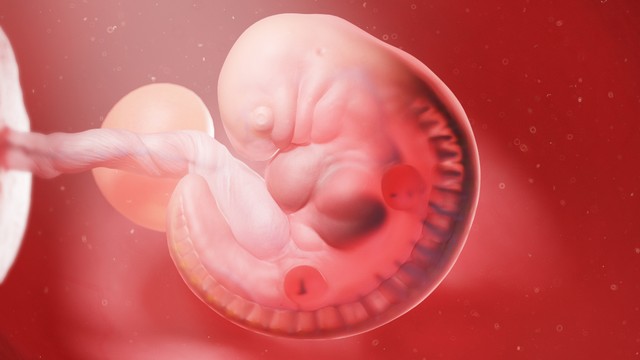

Sự phát triển của thai nhi